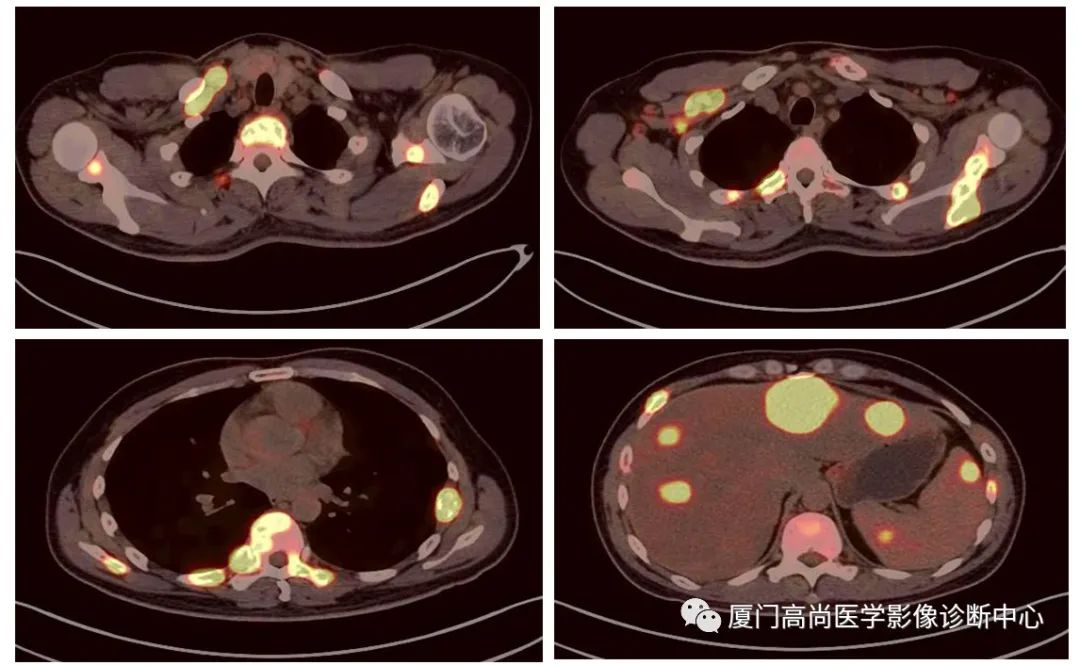

病例1:某男士,36歲,半年前摔傷,當(dāng)時(shí)無大礙,近幾個(gè)月來腰腿痛,并逐漸加重,消瘦10多斤。MRI檢查發(fā)現(xiàn)腰椎、骨盆 骨質(zhì)異常信號(hào),查血各項(xiàng)腫瘤標(biāo)記物正常,因診斷不清而來做PET/CT檢查

淋巴瘤在骨骼、肝臟、脾臟、淋巴結(jié)表現(xiàn)

肝臟、脾臟、骨骼淋巴瘤病灶

骨骼、腋窩淋巴結(jié)病灶

PET/CT發(fā)現(xiàn) :全身多發(fā)淋巴結(jié)腫大,F(xiàn)DG攝取增高;肝臟、脾臟多發(fā)低密度結(jié)節(jié), FDG攝取增高;雙側(cè)扁桃體腫大,F(xiàn)DG攝取增高;全身多處骨骼破壞,F(xiàn)GD攝取增高;上述考慮為淋巴瘤

經(jīng)淋巴結(jié)穿刺活檢 :病理診斷為彌漫大B細(xì)胞淋巴瘤